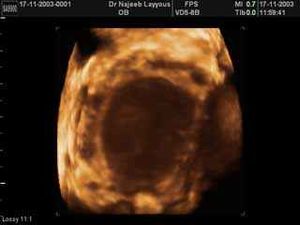

- جهاز الألتراساوند المهبلي: ممكن أن يكشف عن وجود أكياس دموية على المبيضين.